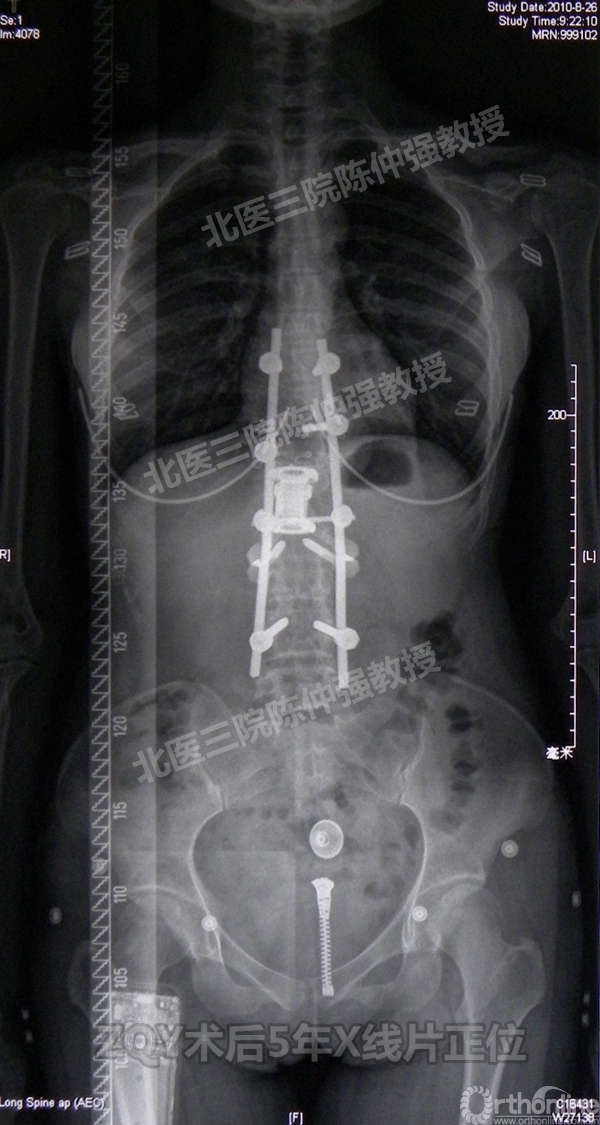

ZQY术后5年

患者女性17岁,胸腰椎陈旧结核性侧后凸畸形,局部呈“麻花状”扭转,无神经功能受损表现。2005年,陈仲强教授带领团队实施后路+侧前方联合入路脊柱节段切除、双轴旋转矫形术。术后患者外观显著改善,神经功能正常。术后随访证实患者截骨矫形节段骨性融合良好,矫形效果持续良好。